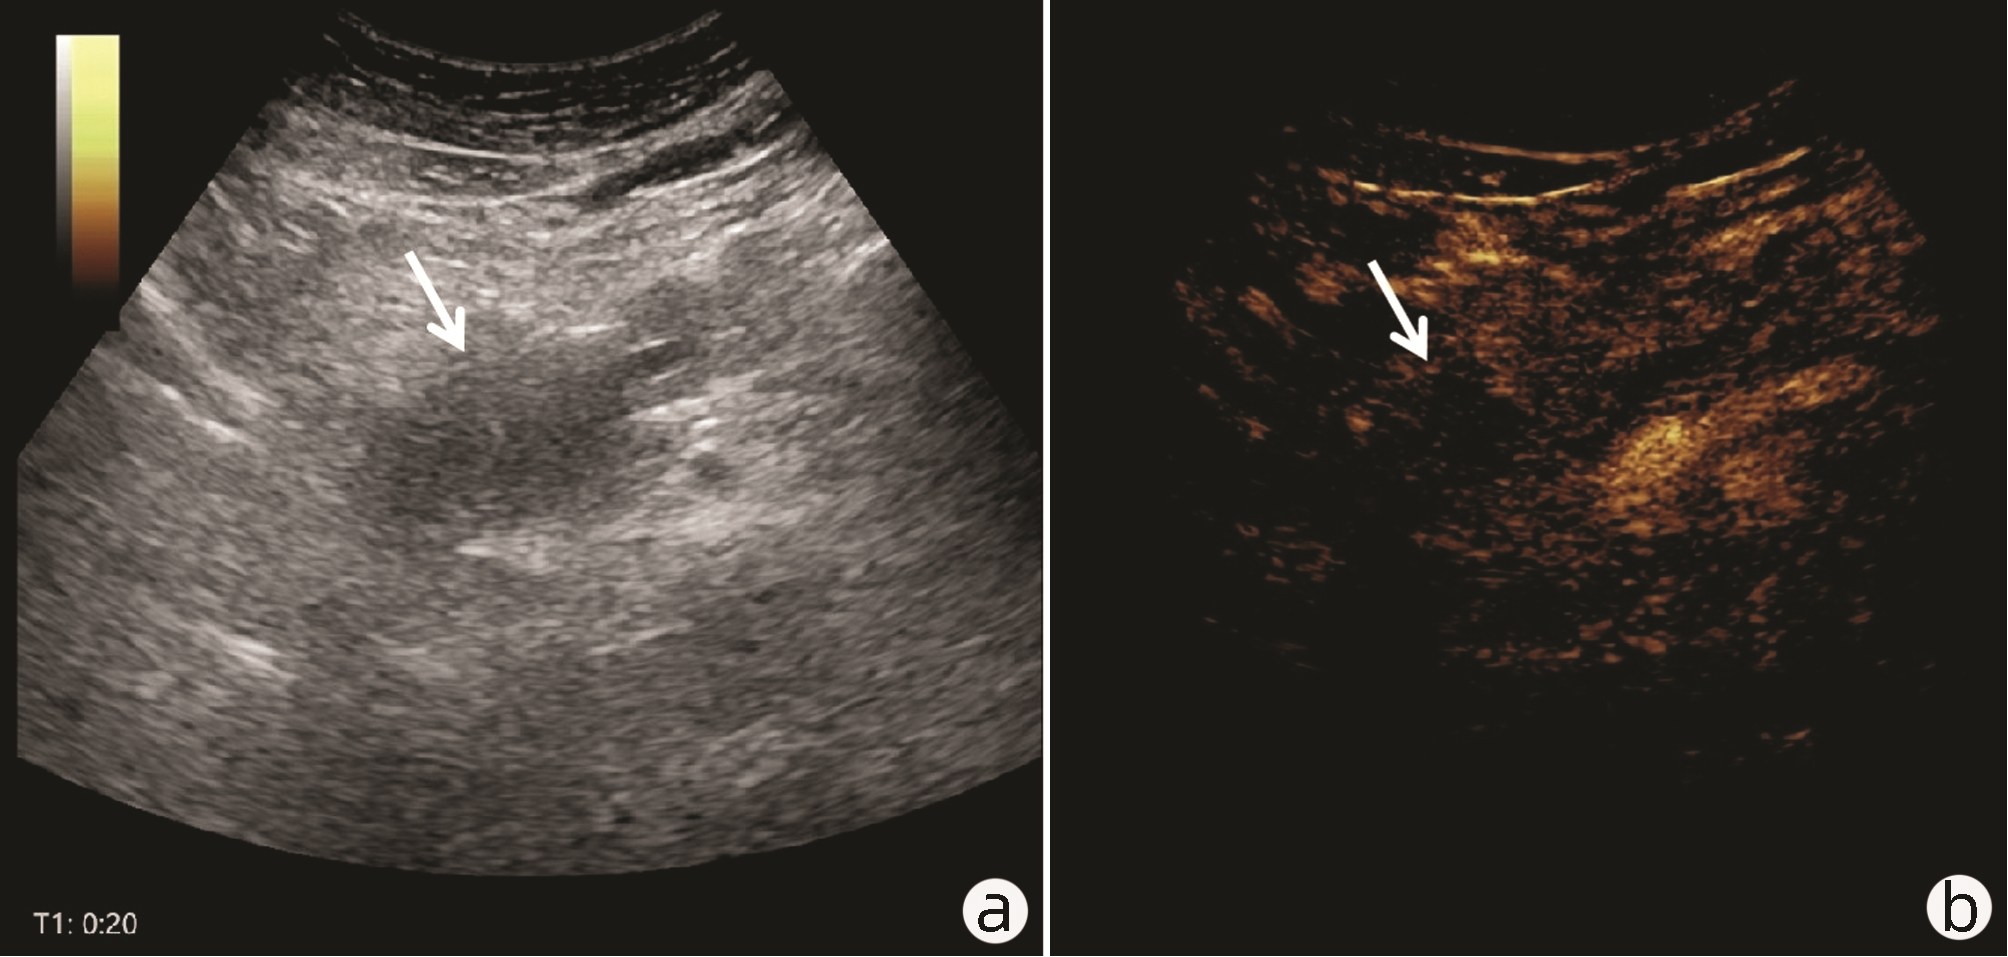

Value of 18F-FDG PET/CT, contrast-enhanced ultrasound, and their combined use in differential diagnosis of benign and malignant pancreatic lesions: A comparative study

Lichun ZHENG, Xiaoming ZHANG, Tianying YU, Jie LI, Xiaoqian DENG, Xiangliu OUYANG

2022, 38(12): 2774-2779. DOI: 10.3969/j.issn.1001-5256.2022.12.017

Abstract(2330) HTML (1630) PDF (3391KB)(64)

Objective  To assess the value of 18F-FDG PET/CT, contrast-enhanced ultrasound, and their combination in the differential diagnosis of benign and malignant pancreatic lesions.  Methods  A retrospective analysis was performed on patients with pancreatic lesions who underwent18F-FDG PET/CT and contrast-enhanced ultrasound who were admitted to Tangshan Gongren Hospital from January 2015 to December 2020. The imaging results were confirmed by pathology examination to evaluate diagnostic sensitivity, specificity, accuracy, positive and negative predictive value. The t-test was used for comparison of continuous data between two groups, and the chi-square test was used for comparison of categorical data between groups.  Results  There were 83 malignant lesions and 25 benign lesions in 108 patients. The sensitivity, specificity, accuracy, positive and negative predictive value were 86.75%, 80.00%, 85.19%, 93.51% and 64.52% for 18F-FDG PET/CT; and 69.88%, 76.00%, 71.30%, 90.63% and 43.18% for contrast-enhanced ultrasound, respectively. The two methods differed significantly in sensitivity and accuracy (all P < 0.05), but not in specificity, negative and positive predictive value (all P > 0.05). When combined with the contrast-enhanced ultrasound, 18F-FDG PET/CT had an increased sensitivity, specificity, accuracy, positive and negative predictive value of 90.36%, 84.00%, 88.89%, 94.94% and 72.41%, respectively, though this was not statistically significant due to the increased signal of blood supply in the lesions.  Conclusion  18F-FDG PET/CT has a better performance than contrast-enhanced ultrasound in the differential diagnosis of benign and malignant pancreatic lesions, and their combination can improve the diagnostic value.